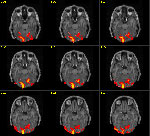

fMRI

Die Demoversion der Anwendung funktionelle Hirnbilddaten basiert

auf den Beispielprogrammen von Prof. Dr. Dr.

Bernarding Stand Juli 2006. Sie soll einen ersten Eindruck

vermitteln wie eine Integration in MediGRID und die Benutzerfühung

im Portal aussehen könnte.